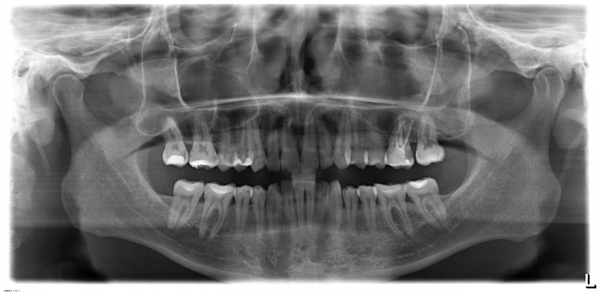

Разошлось мнение двух врачей: одна считает, что кариес на шестнадцатом есть, вторая, что его нет. На рентгене, на шестнадцатом виден темный участок, то есть, скорее кариес есть, чем его нет.

С вашей точки зрения он скорее есть, чем его нет? (речь идет не о поверхностном кариесе, который на рентгене нельзя увидеть, а о более глубоком: среднем или глубоком). Снимок был сделан до лечения.

На снимке в области семнадцатого и двадцать шестого зуба, под пломбой, наблюдается полость, которая неграмотно препарирована перед установкой пломбы, чувствительность и некий дискомфорт при надкусывании или пережевывании твердой пищи связано именно с этим. Что касается шестнадцатого зуба, я считаю, что полость имеется, но все-таки необходим еще и очный прием.